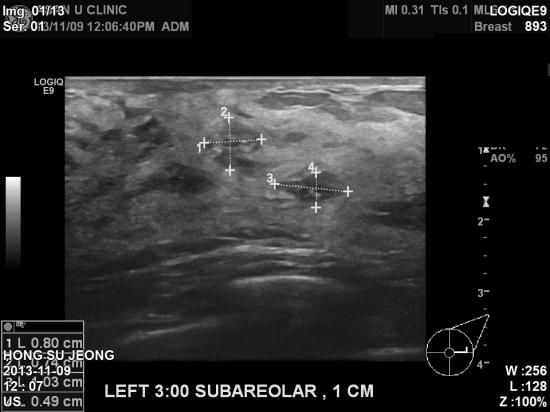

직장검진에서 실시한 유방초음파상 이상소견있어

진료위해 본원에 내원하신 31세 여자분이십니다.

어머님이 유방암으로 수술받으신 가족력이 있으신데다가,

종양의 크기는 작지만 경계가 불분명하고 석회화를

동반한 종양이있어 2군데 조직검사 시행결과 2혹 모두 유관상피내암종으로 진단되었습니다.